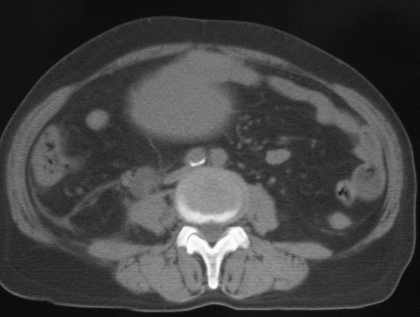

女56岁以右输尿管结石入院

病灶位于下腹部盆腔,从子宫与膀胱明显受压后移看,应该来源于盆腹腔的占位,病灶实性部分密度均匀,左侧可见低密度灶,建议增强扫描,考虑:间叶性肿瘤,或硬纤维瘤,输尿管下段结石伴上段输尿管扩张

增强ct或mr检查。

支持卵巢囊腺瘤;输尿管结石.建议增强.

今天病人已经手术证实为右附件囊肿,右侧输尿管第二狭窄处结石伴梗阻!!!

[病理诊断] CT11527:右附件囊肿,右侧输尿管结石。